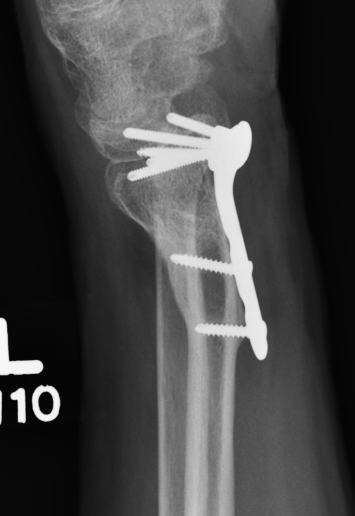

Tendon rupture

Azzi et al Plastic Reconst Surg 2017

- systematic review of tendon rupture after surgery

- 56 studies and 6000 patients

- volar plates: tendon rupture 1.5%, tenosynovitis 4.5%

- dorsal plates: tendon rupture 1.7%, tenosynovitis 7.5%

EPL rupture

Etiology

Minimally displaced distal radius fracture treated nonoperatively

- interrupts blood supply at a watershed area

- between 3 weeks and 3 months post injury

- ruptures distal to extensor retinaculum at Lister's tubercle

Dorsal plates

Long screws in volar plate

Rheumatoid arthritis